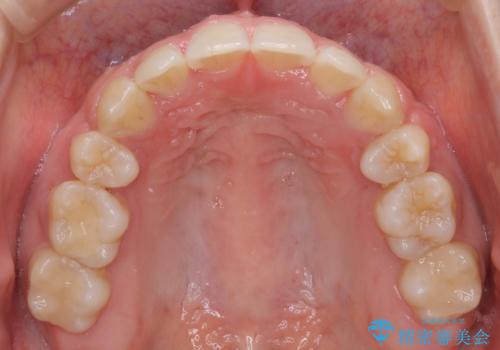

- 口元をさげたいという主訴で来院されました。4番の歯を4本抜歯し、審美装置にて治療をしました。

抜歯をしたことで口元の突出感が改善しました。約2年を予定していた矯正ですが、約1年という短い期間で終了できました。